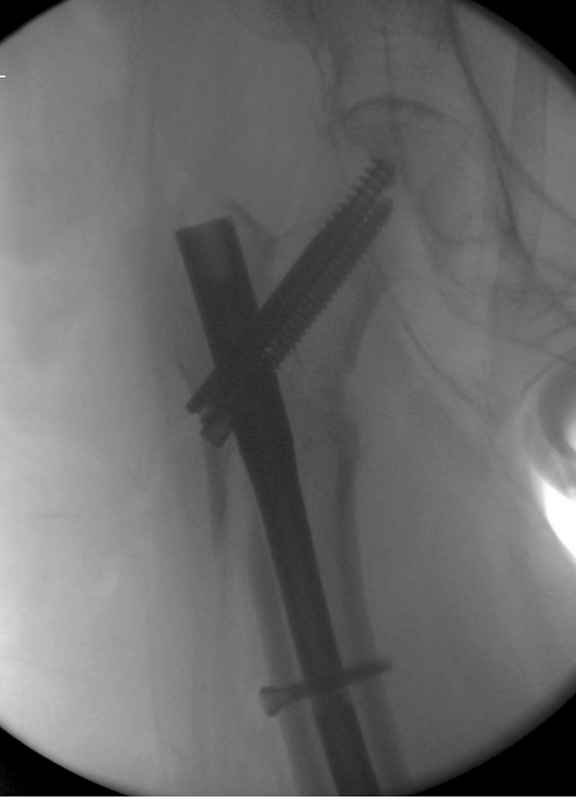

Re: Чрезвертельный перелом бедра

Здесь 83 года, травма в результате падения